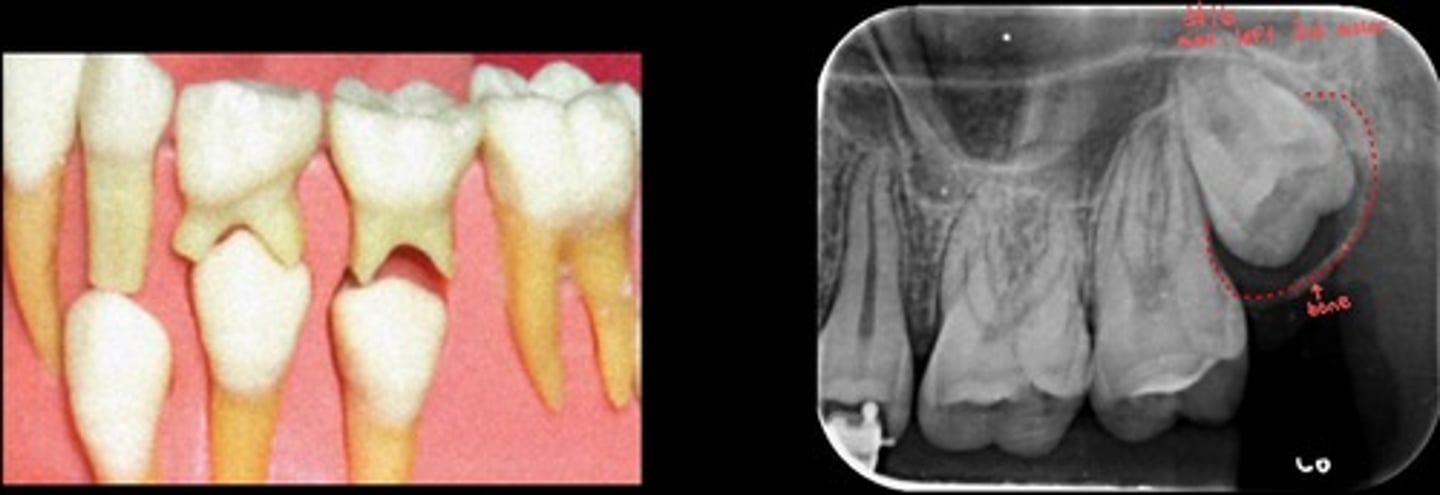

Hypercementosis

What are the red arrows representing?

What are the red dots representing?

Dental follicle space